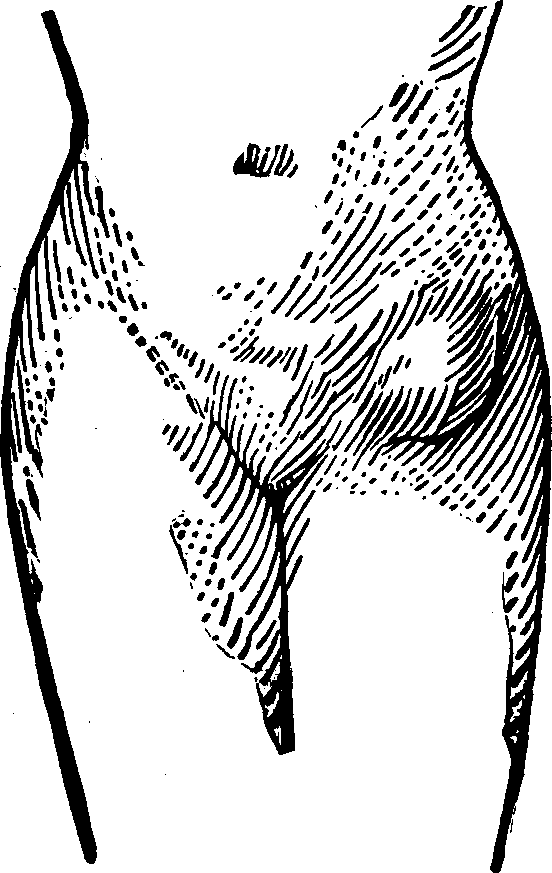

Fig.

24. A representation of the superficial layer of muscles on the anterior

portion of the body.

Fig.

25. A representation of the superficial layer of muscles on the posterior

portion of the body.